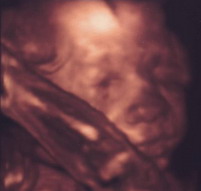

Edi, Bibar: gratu a jó UH-os hírekhez, Kamilláról várjuk ám a képeket, Boti pedig édes kis ManóPofi!